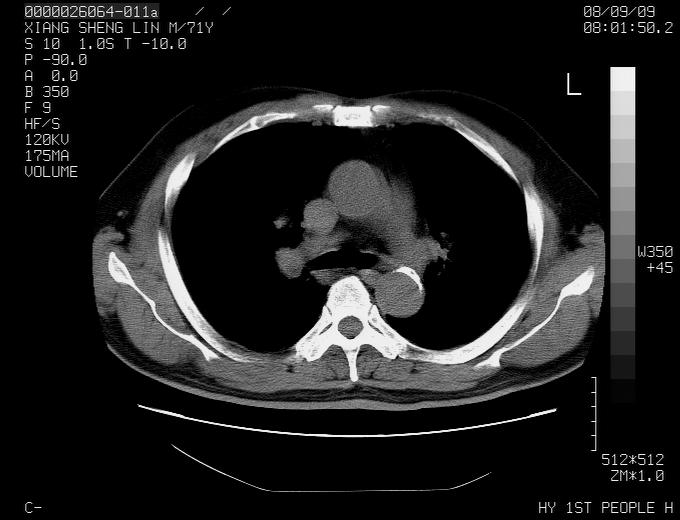

标题: CT15869:男性,71岁,因咳嗽而就诊,请讨论右上肺病变性质 [打印本页]

标题: CT15869:男性,71岁,因咳嗽而就诊,请讨论右上肺病变性质

患者,男性,71岁,因咳嗽而就诊,

典型的右肺中心性肺癌并纵隔淋巴结转移

右肺中心性肺癌并纵隔淋巴结转移可能性大!

病灶中等程度强化 还是支持肺癌诊断

考虑右肺中心性肺癌并右肺门及纵隔淋巴结转移。

1,右肺中心型ca,气管隆突旁淋巴结转移。

2,右膈明显抬高,建议肝脏扫描排除转移或原发灶。